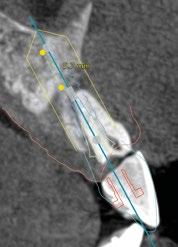

En este caso, podemos ver que tenemos un defecto óseo vestibular, se trata de un defecto de una sola pared de la zona a implantar.

Intentamos planificar un implante inmediato y observamos la posibilidad de tener un buen anclaje apical por lo tanto nuestra primera opción va a ser la realización de un implante post extracción con regeneración de la pared vestibular mediate xenoinjerto óseo e injerto de tejido conectivo para mejorar el biotipo. (Figura 9)

En el caso de obtener suficiente torque, podríamos incluso valorar la opción de cargar dicho implante. En este caso lo que hacemos es planificar también un pilar con el fin de trabajar nuestra prótesis a nivel gingival, siguiendo la filosofía de “One Abutment-One Time (OAOT)”.

Lo realmente extraordinario de este software de diagnóstico y planificación es que en una sola imagen tenemos total control de la posición de nuestro implante y de nuestro pilar, en función del hueso de la encía y de la futura restauración. Por lo tanto vamos a realizar una implantología protética, y biológicamente guiada. (Figura 10)

Otra de las ventajas que nos ofrece el software de diagnóstico y planificación DTX

StudioTM Implant es la posibilidad de diseñar una férula quirúrgica y exportarla con el fin de poder imprimirla de manera local y acortar así los tiempos de preparación. (Figuras 11 y 12)